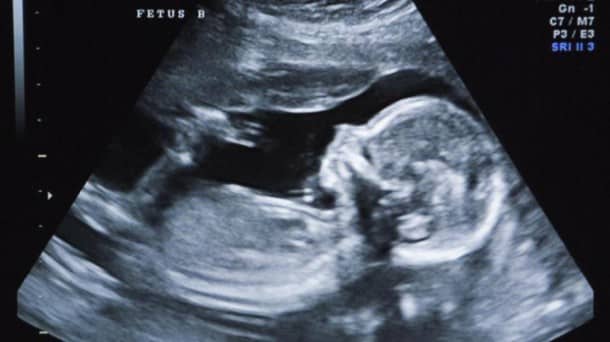

C’est un cas extrêmement rare qui se produit toutes les 500 000 naissances. Une équipe médicale de Hong Kong relate dans le Hong Kong Medical Journal avoir trouvé des foetus jumeaux dans l’abdomen d’une enfant qui venait juste de naître.

Les foetus âgés d’environ 10 semaines ont pu être retirés du corps du bébé quelques semaines après sa naissance. La petite fille s’est bien remise de l’opération et se porte aujourd’hui très bien.

Les médecins ont toutefois encore du mal à expliquer ce phénomène et même le terme de « foetus » fait encore débat au sein de la communauté médicale qui envisage qu’il puisse s’agir de tumeurs évoluées également appelées tératomes.